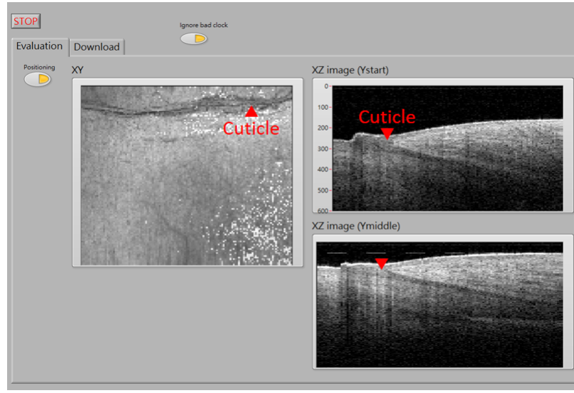

光學同調斷層血管造影術(optical coherence tomography angiography, OCTA)作為光學同調斷層掃描術(optical coherence tomography, OCT)的延伸技術,能通過檢測血管內移動的紅血球來區分血管與周圍的靜態組織,進而提供高解析度的生物組織三維視圖。OCTA 的技術優勢包括1-1.5毫米的穿透深度、10-15微米的空間解析度、快速的影像採集速度及深度分層的3D成像,並且不受膚色差異的影響,使其成為血管成像的理想選擇。因此,本實驗室透過量測人體甲褶區域的OCTA影像,深入探討末梢微血管組織與心血管系統的健康狀態及功能性關聯,期望為臨床醫學提供全新的診斷觀點與參考標準。